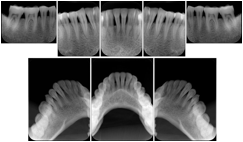

3. A dental provider wishes to capture a series of DICOM IO images for the patient’s dentition. The tooth morphology, teeth are divided into molars, premolars, canines and incisors, and a number of images for each jaw. The anatomic information was captured utilizing the triplet of schema. This standard code sequence is based on ISO 3950-2010, Dentistry - Designation system for teeth and areas of the oral cavity.

Every IO image should have anatomic information either through the primary or modifier sequence.

In most standard cases, images are oriented in structured layouts. These structured displays are useful to be shared between providers for reference purposes.

Table OO.1.1-1 shows structured display standard templates, where Viewset ID is based on the Japanese Society for Oral and Maxillofacial Radiology (JSOMR) classification provided by JIRA (Japan Medical Imaging and Radiological Systems Industries Association, www.jira-net.or.jp). Expected or typical teeth to be imaged location, region and designation codes are based on ISO 3950-2010, Dentistry - Designation system for teeth and areas of the oral cavity. For all the hanging protocols listed in OO.1.1-1, the value to use for Hanging Protocol Creator (0072,0008) is "JSOMR" and the value to use for Hanging Protocol Name (0072,0002) does not include "JSOMR" (e.g., "DL-S001A", not "JSOMR DL-S001A").